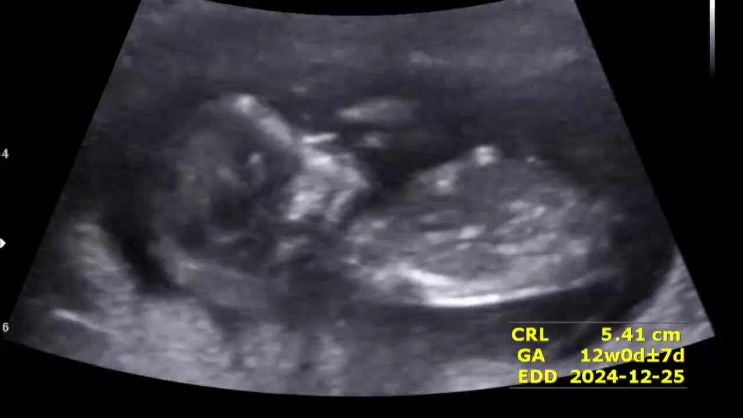

[11주2일]1차 기형아검사/니프티검사(더맘스캐닝플러스)

11주차 1차 기형아검사/ 니프티 검사(더맘스캐닝플러스) 기다리고 기다려온 2주 뒤, 남편과 함께 한빛여성...